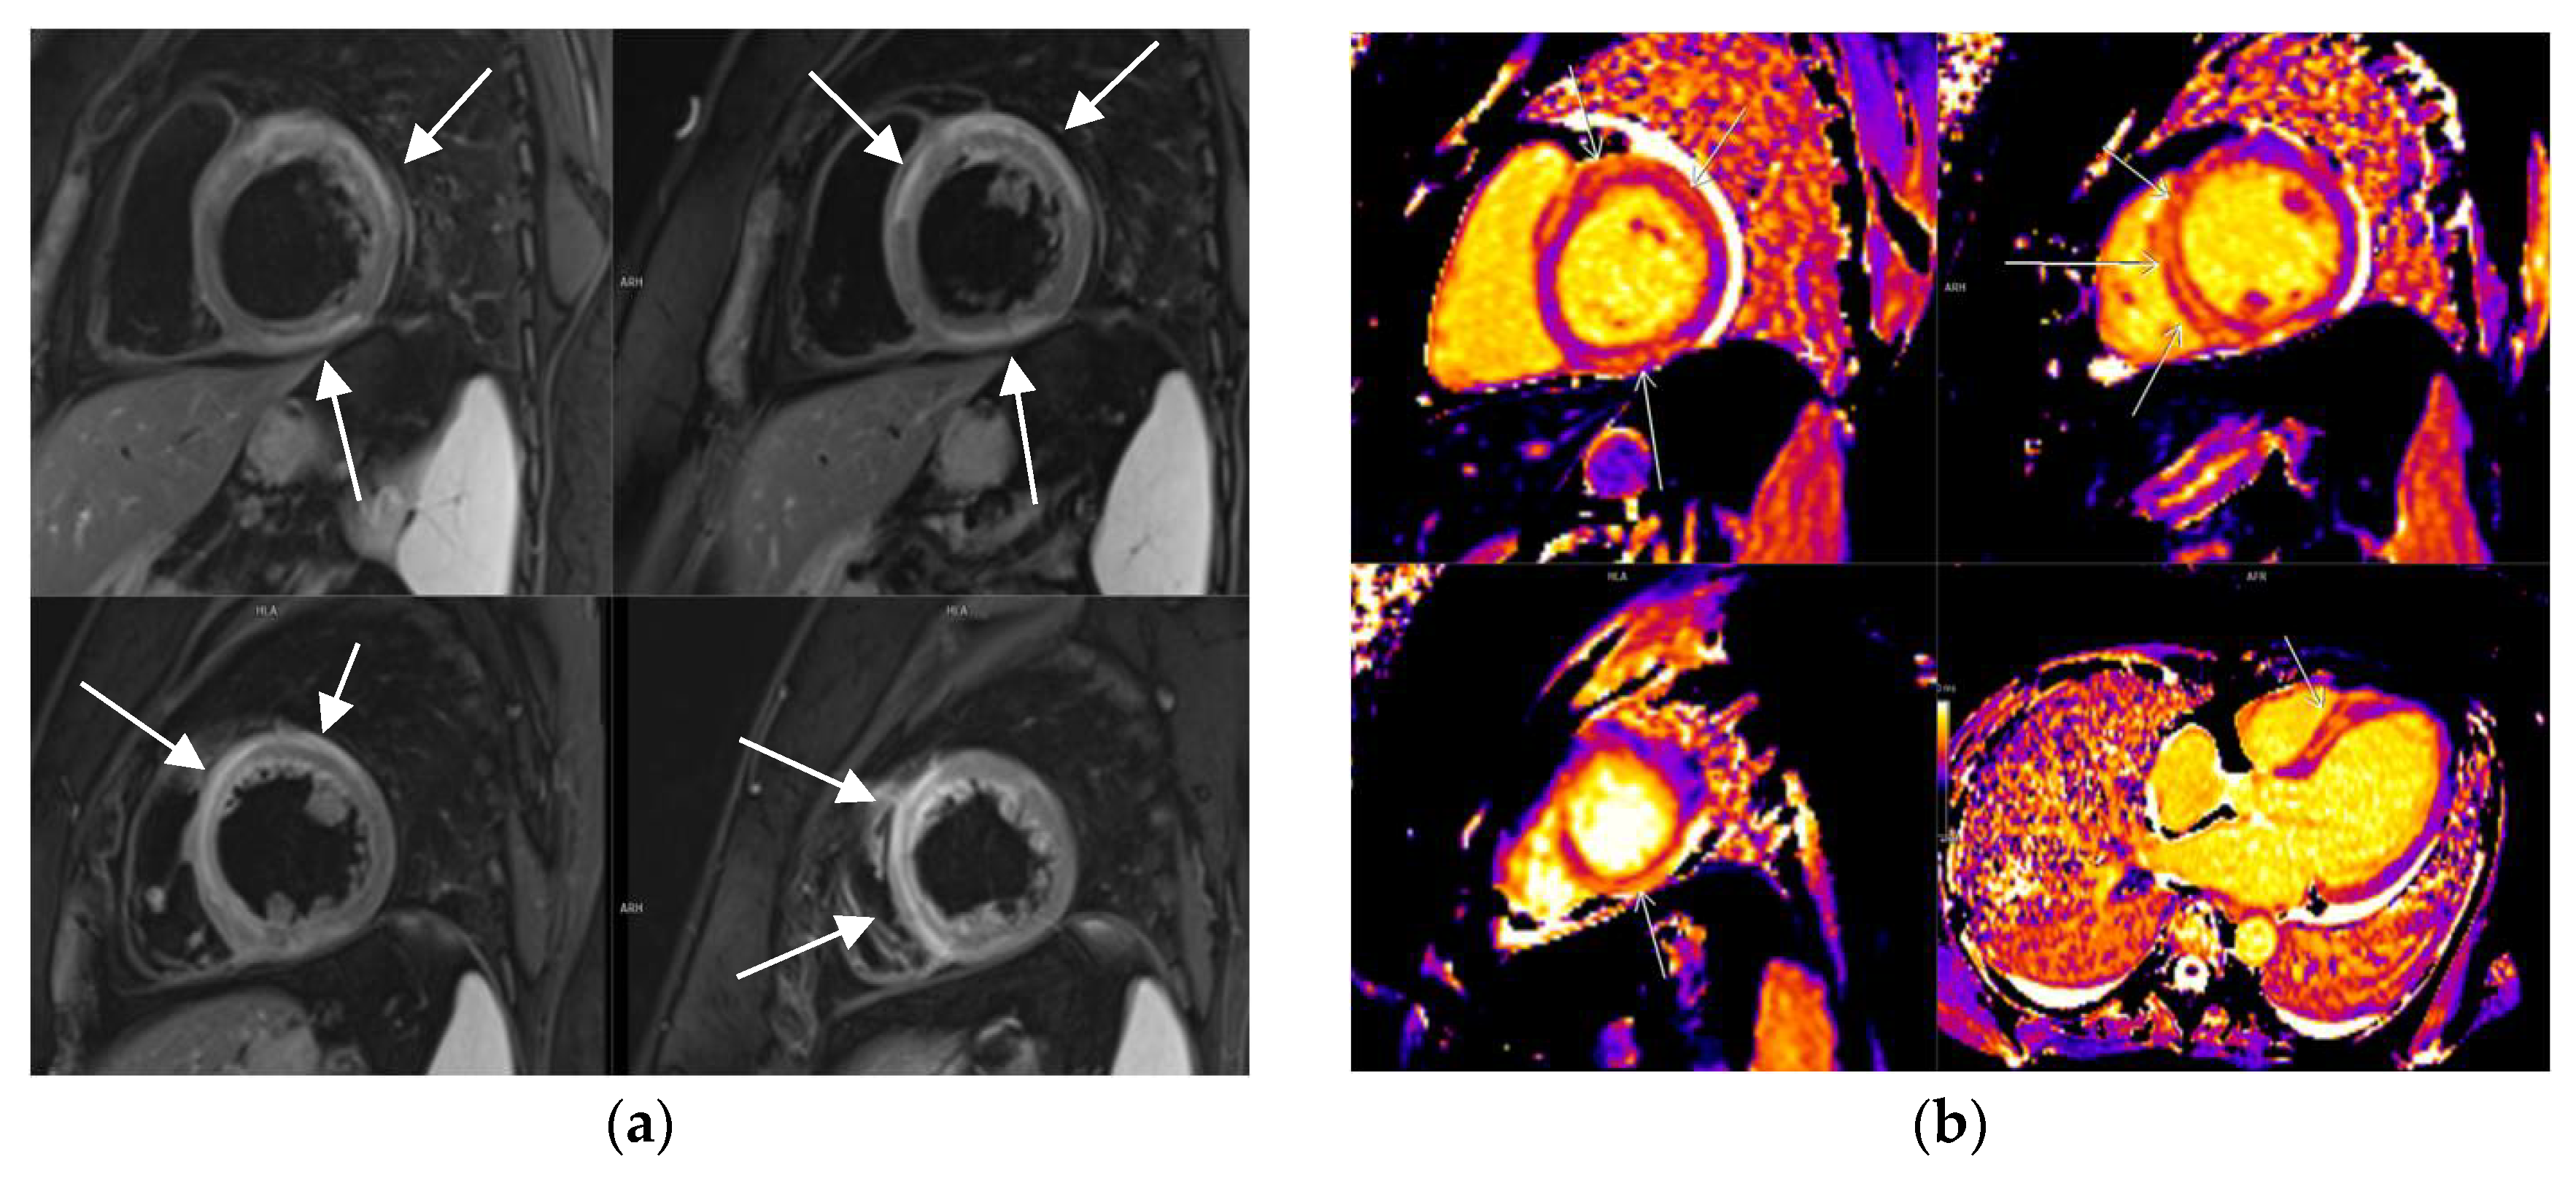

3.2. CMR Findings

3.5. LGE Localization